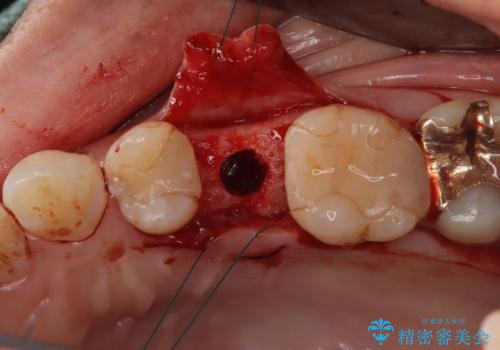

- 根管治療をしている歯が破折し、抜歯となってしまいました。

抜歯した部位に対して、はじめに可撤性部分義歯,ブリッジ、インプラントによる治療方法とそれぞれの利点と欠点について説明を行った結果、インプラント治療を希望されました。さらに、インプラント治療の術前・術後口腔内管理の重要性、手術内容,費用などを説明し、十分なインフォームド・コンセントを得たうえで治療を開始しました。